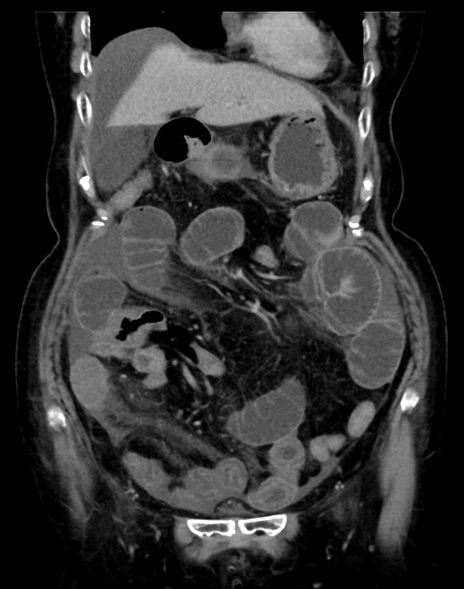

症例13 CT(冠状断像)1日半後